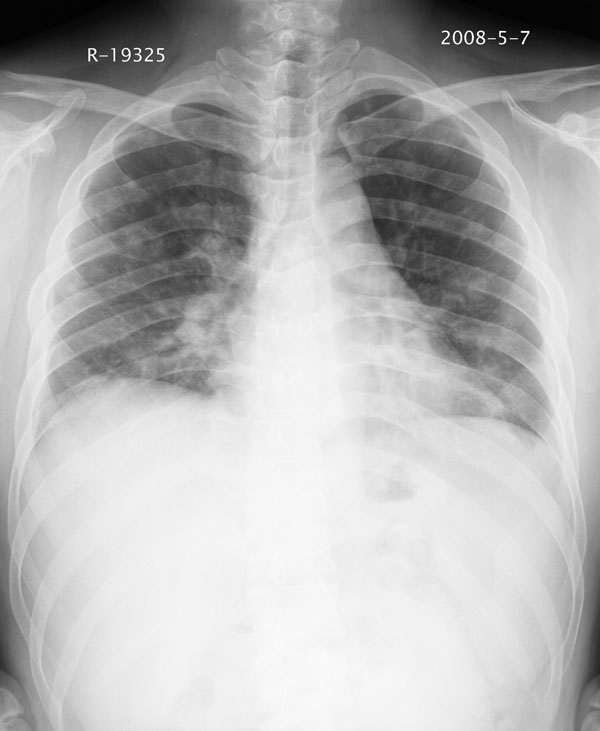

患者男性 35 主因发热咳嗽四天,血象不高,心肺听诊未见异常,无其它病史及传染病接触史。

一周后复查胸片基本正常

两肺散在大小不等小结节影,下野较多,纵隔淋巴结增大。考虑:1、慢性血播性肺结核;2、霉菌病?3转移瘤待排。

该病人肺内多发结节,右肺门似有肿大淋巴结,肺结节病也要考虑

两肺多发结节,部分病灶边缘不清,且示毛玻璃影。分布特点为沿血管支气管分布。

结合临床考虑;1,炎性肉芽肿性病变;霉菌?过敏性肺炎?2,韦格氏肉芽肿。3,转移瘤。

补充一下各种检查结果,病人无痰,胸闷,ppd及结核抗体阴性,wbc7.5x10的9次方,血沉22mm/h,crp及抗链o阳性。

经一周抗炎抗病毒治疗复查胸片示病变大部吸收,基本恢复正常,未做气管镜检查,考虑为炎性变或霉菌感染。